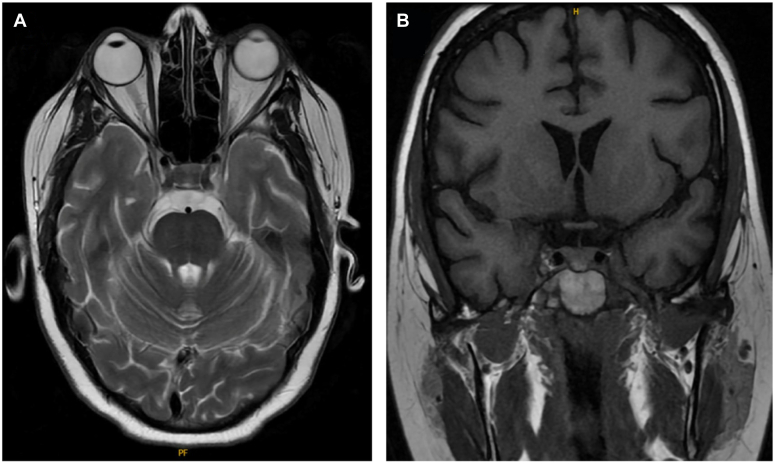

An 18-year-old woman presented with mood disturbances, weight gain, and fatigue for 6 months. Workup revealed high levels of urinary free cortisol (>900 μg/dL; normal range, <45 μg/dL) and midnight salivary cortisol (0.755 μg/dL; normal range, <0.09 μg/dL). The ACTH and cortisol levels remained elevated after a low-dose dexamethasone suppression test. Magnetic resonance imaging of the pituitary gland did not reveal any adenoma and inferior petrosal sinus sampling showed no central-to-peripheral gradient. A diagnosis of EAS was made. Subsequent body imaging noted a 1-cm lung nodule. Due to symptoms of severe hypercortisolism including hypokalemia and worsening mood changes, the patient was started on metyrapone as a bridge to surgery. A few weeks later, the patient underwent successful surgical resection, after which symptoms promptly resolved. Pathology report later confirmed an atypical lung carcinoid tumor. The patient remained in remission at 1-year follow-up.